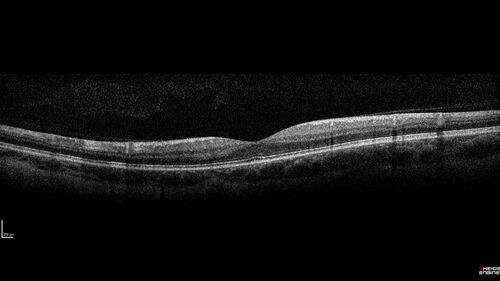

Myelinated Nerve Fiber Layer - Peripheral

43 year old man with floaters

MNFL Atypical - peripheral